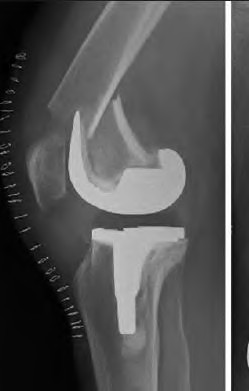

A patient presents with a palpable, painful 'catch' and an audible pop during active extension of the knee from 40 degrees to 30 degrees following a posterior-stabilized (PS) Total Knee Arthroplasty (TKA). What is the most likely etiology?